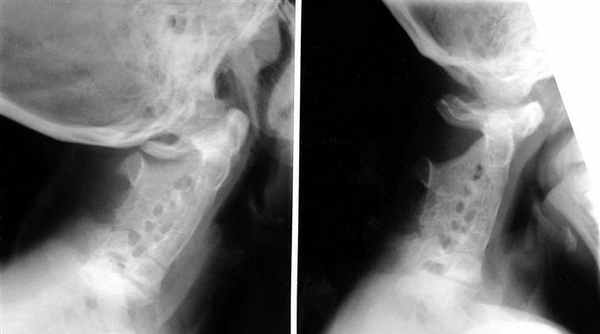

Диагностируется с помощью методов изображений (рентген). МРТ (магнитно-резонансная томография) – делается для характеристики открытых пространств между позвонками. Он также обнаруживает степень аномального слияния позвонков с поражением спинного мозга. Дополнительные исследования назначаются для определения и выявления аномалий.

Синдром Клиппеля-Фейля (СКФ) — это врожденная анатомическая аномалия шейного отдела позвоночника, которая характеризуется сращением двух или более шейных позвонков. Также этот синдром называют синдромом короткой шеи.

Пациенты с СКФ имеют деформацию шейного отдела при рождении, но обычно это диагностируются в гораздо более позднем возрасте, например, во время проведения рентгенологического исследования по другому поводу. Чаще всего данный синдром диагностируется при появлении жалоб, основными являются боль и неврологические симптомы. Также могут быть выполнены КТ и МРТ шейного отдела.

Костная система. Наблюдается различная степень синостозирования одного или большого числа шейных позвонков.

Лабораторные данные. Аномалия Клиппеля — Фейля является наиболее характерной чертой заболевания. Ретгенологически отмечается синостозирование нескольких шейных позвонков. Могут также наблюдаться расщепление позвоночника, высокое положение одной или обеих лопаток (деформация Шпренгеля), кифосколиоз. Встречались также половинные позвонки (Witzel, Cross, Pfaffenbach, Stark, Borton).

Синдром Клиппеля - Фейля (s. Klippel - Feil), синдром врожденной костной кривошеи, врожденный синостоз шейно- грудных позвонков, синдром короткой шеи.

Врожденное наследственное заболевание, передается по аутосомно- доминантному типу, проявляется с рождения. В основе аномалии Клиппеля - Фейля лежит нарушение процесса сегментации и дифференциации мезенхимы. Сущность деформации заключается в обширной кенкрестенции (слиянии) шейных позвонков. Количество шейных позвонков обычно меньше нормы, а общая высота меньше высоты этих позвонков с дисками, что и является причиной укорочения шеи. В эту костную массу могут быть включены и верхние грудные позвонки. Клинически синдром Клиппеля - Фейля представляет собой триаду: короткая шея, низкая граница роста волос на шее (до уровня I грудного позвонка) и резкое ограничение движений головы. При этой патологии наблюдаются и другие врожденные аномалии: высокое стояние лопаток, сколиоз, шейные ребра, кривошея, асимметрия лица и туловища, крыловидные кожно- мышечные складки на боковой поверхности шеи, деформация ключиц. Неврологические осложнения встречаются в виде атрофии мышц плечевого пояса, расстройства чувствительности в области шеи и груди, компрессионного радикулита шейных корешков, синдрома компрессии спинного мозга на уровне шейного утолщения.